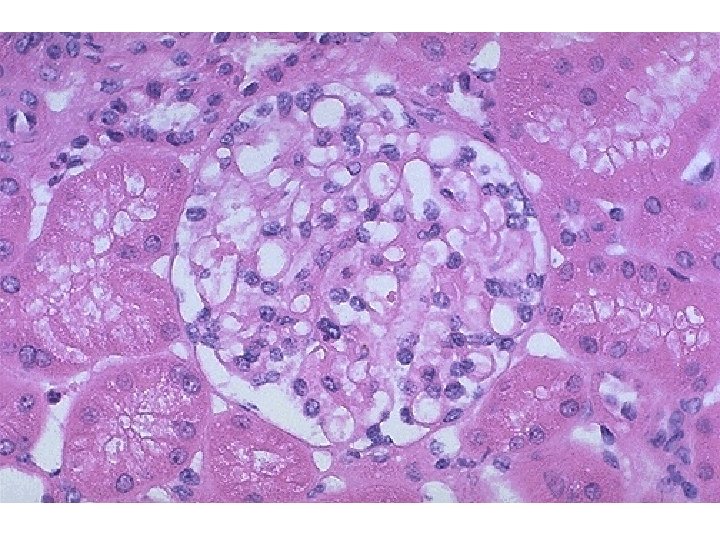

• Microscopically: – Patchy process with periglomerular fibrosis (outside Bowman's capsule) – Interstitial scarring – Scar retraction produces dilatation of castfilled tubules, or "thyroidization").

Chronic pyelonephritis